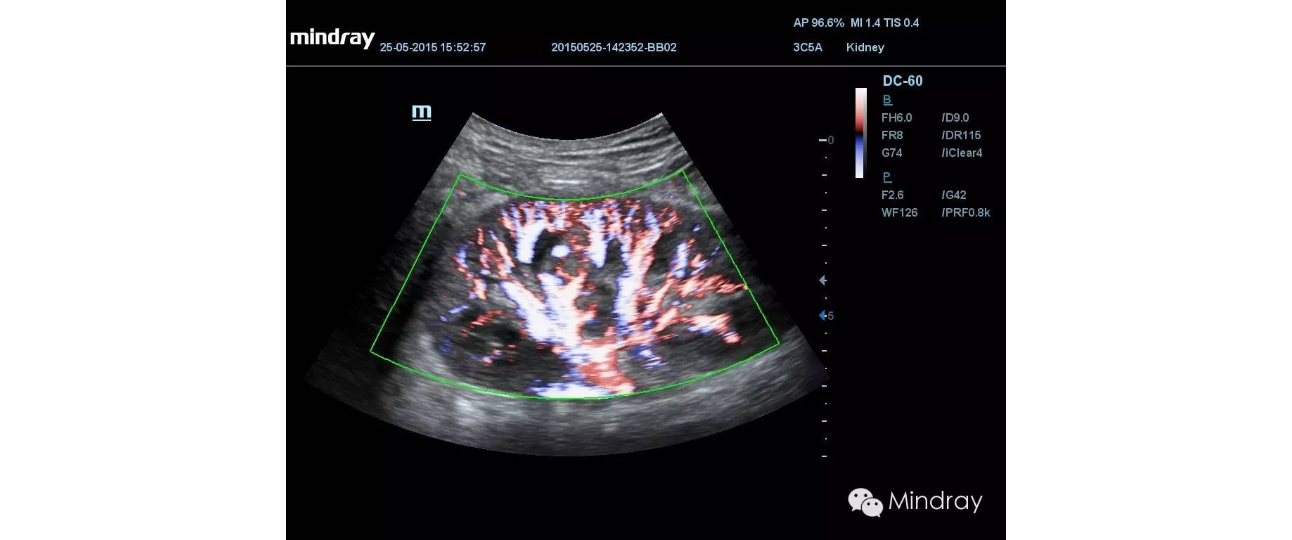

HR Flow

Based on DC-60's shared service capabilities, reliable image quality for patients of various ages and sizes in diverse clinical areas is available all with one intelligent ultrasound machine. Covering general imaging, cardiology and OB/GYN, the DC-60 has professional tools such as Auto IMT, iNeedle, TDI and QA, 4D imaging and Smart OB to help complete daily exams easily and precisely.